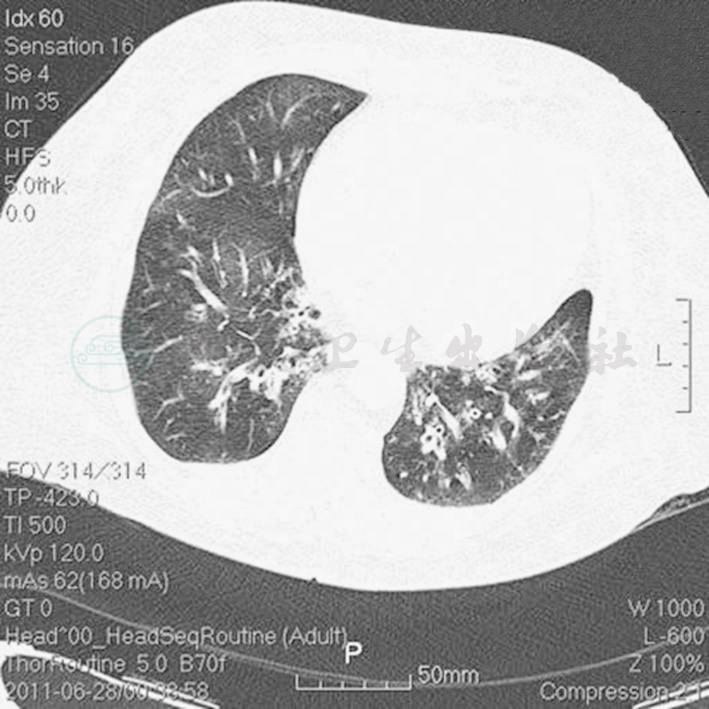

辅助检查:胸部CT(6月28日)(图1):两肺感染性病变,两下肺支气管扩张症伴感染。心电图(6月28日):窦性心律,T波改变。血常规(6月28日):WBC 13.5 × 109/L,N 66.3%,Hb 145g/L;CRP(6月28日)3.8mg/L,PCT(6月28日)5.49ng/ml。

图1 胸部CT(6月28日):两肺感染性病变,两下肺支气管扩张症伴感染